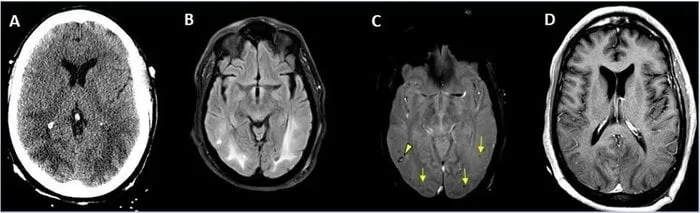

Photo : les dommages au cerveau de la COVID-19 en image

Les médecins travaillent depuis plusieurs mois sur les conséquences de la COVID-19 sur le cerveau. La Société de radiologie d'Amérique du Nord a profité de son congrès annuel pour dévoiler des images des lésions cérébrales que provoque le coronavirus chez certains patients.

Une étude multi-institutionnelle, portant sur près de 40 000 patients hospitalisés pour la COVID-19 de 7 hôpitaux universitaires américains et 4 européens, a mis en évidence que 1% des malades pris en charge sont susceptibles de développer des complications au niveau du système nerveux central.

Les patients avaient un âge moyen de 66 ans. Plusieurs d’entre eux présentaient des comorbidités telles que l'hypertension, des maladies cardiaques ou du diabète. La cause la plus fréquente d'admission était la confusion, l'altération de l'état mental et la fièvre. Les examens d’imagerie ont révélé qu'il y avait 442 résultats de neuro-imagerie aiguë qui étaient très probablement associés à l'infection virale.

L’AVC : la complication la plus fréquente

"Pour tous les patients hospitalisés qui ont subi une imagerie telle qu'une IRM ou une tomodensitométrie du cerveau, l'examen était positif environ 10 % du temps", a précisé le Dr Scott Faro. "L’incidence de 1,2% signifie qu’un peu plus d’un patient sur 100 admis à l’hôpital avec COVID-19 va avoir un problème cérébral quelconque", conclut-il.

Les troubles neurologiques les plus observés étaient l'accident vasculaire cérébral ischémique (62%), suivie de l’hémorragie intracrânienne (3,72%) et de l’encéphalite (0,47%).

Image d'une hémorragie cérébrale observée chez une femme de 56 ans atteinte de la covid-19

Image des complications cérébrales observées chez un homme de 65 ans atteint de la covid-19